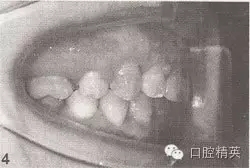

参见图9-33 双侧后牙锁颌矫治前后

A.双侧后牙锁颌矫治前